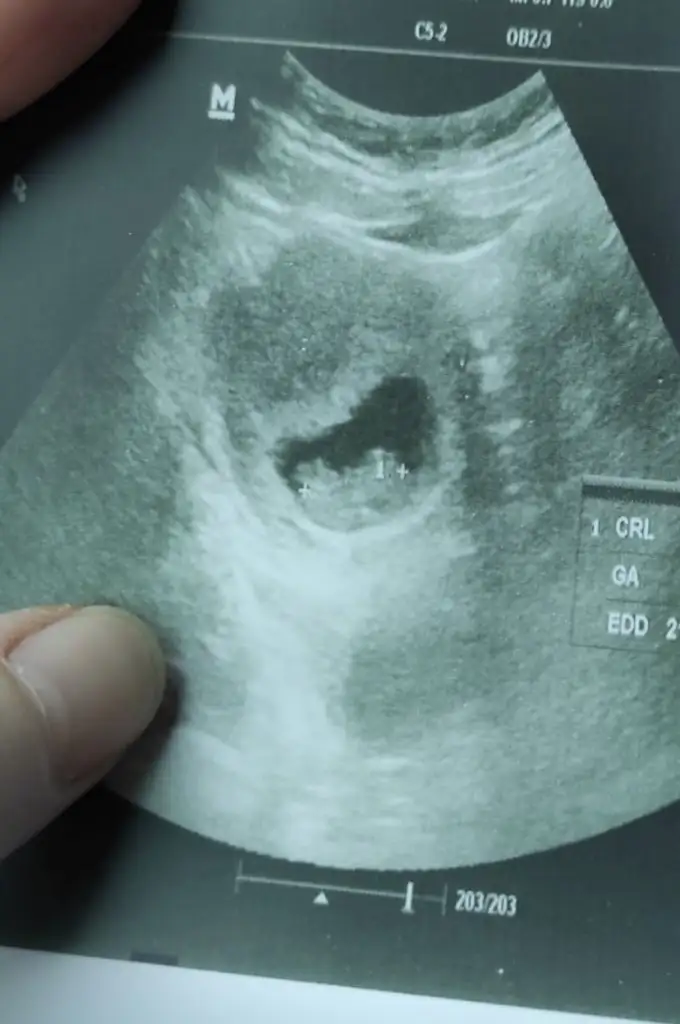

Paşa gibi14+1 karnimdan ultrason tekrar bakabilir misin canım